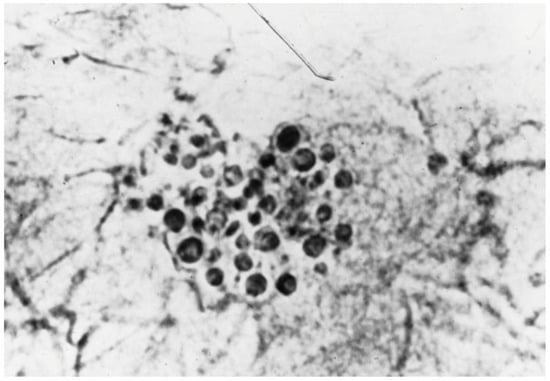

| Histology | Yeast in follicles on PAS/GMS stains | Follicular plugging, inflammation | Neutrophilic infiltrate in follicles |